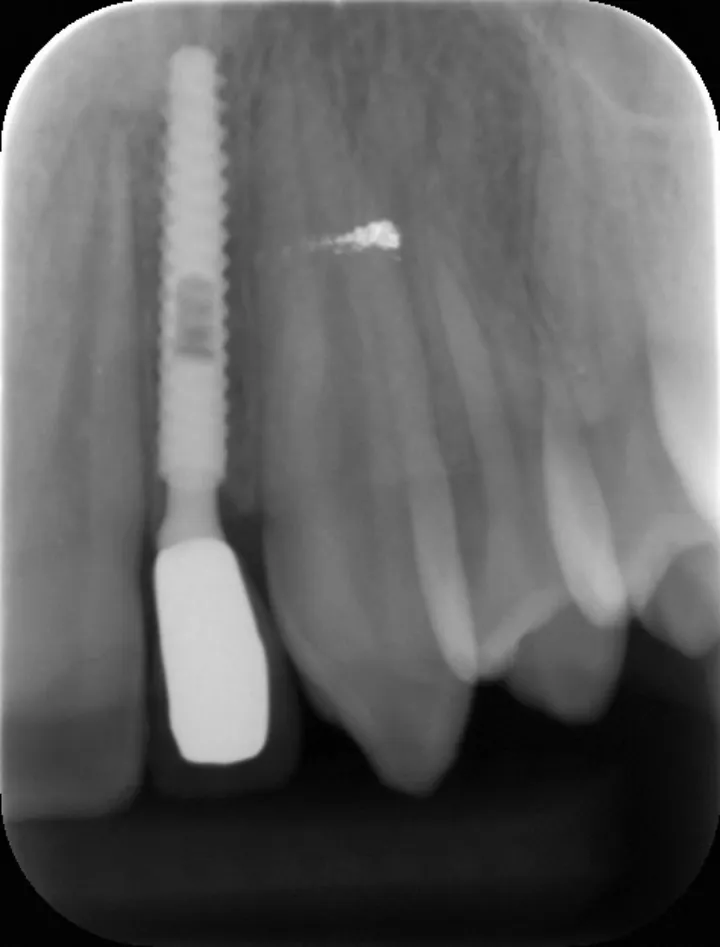

图 19 :12 术后 1 年随访 X 线影像。

图 20 :22 术后 1 年随访 X 线影像。